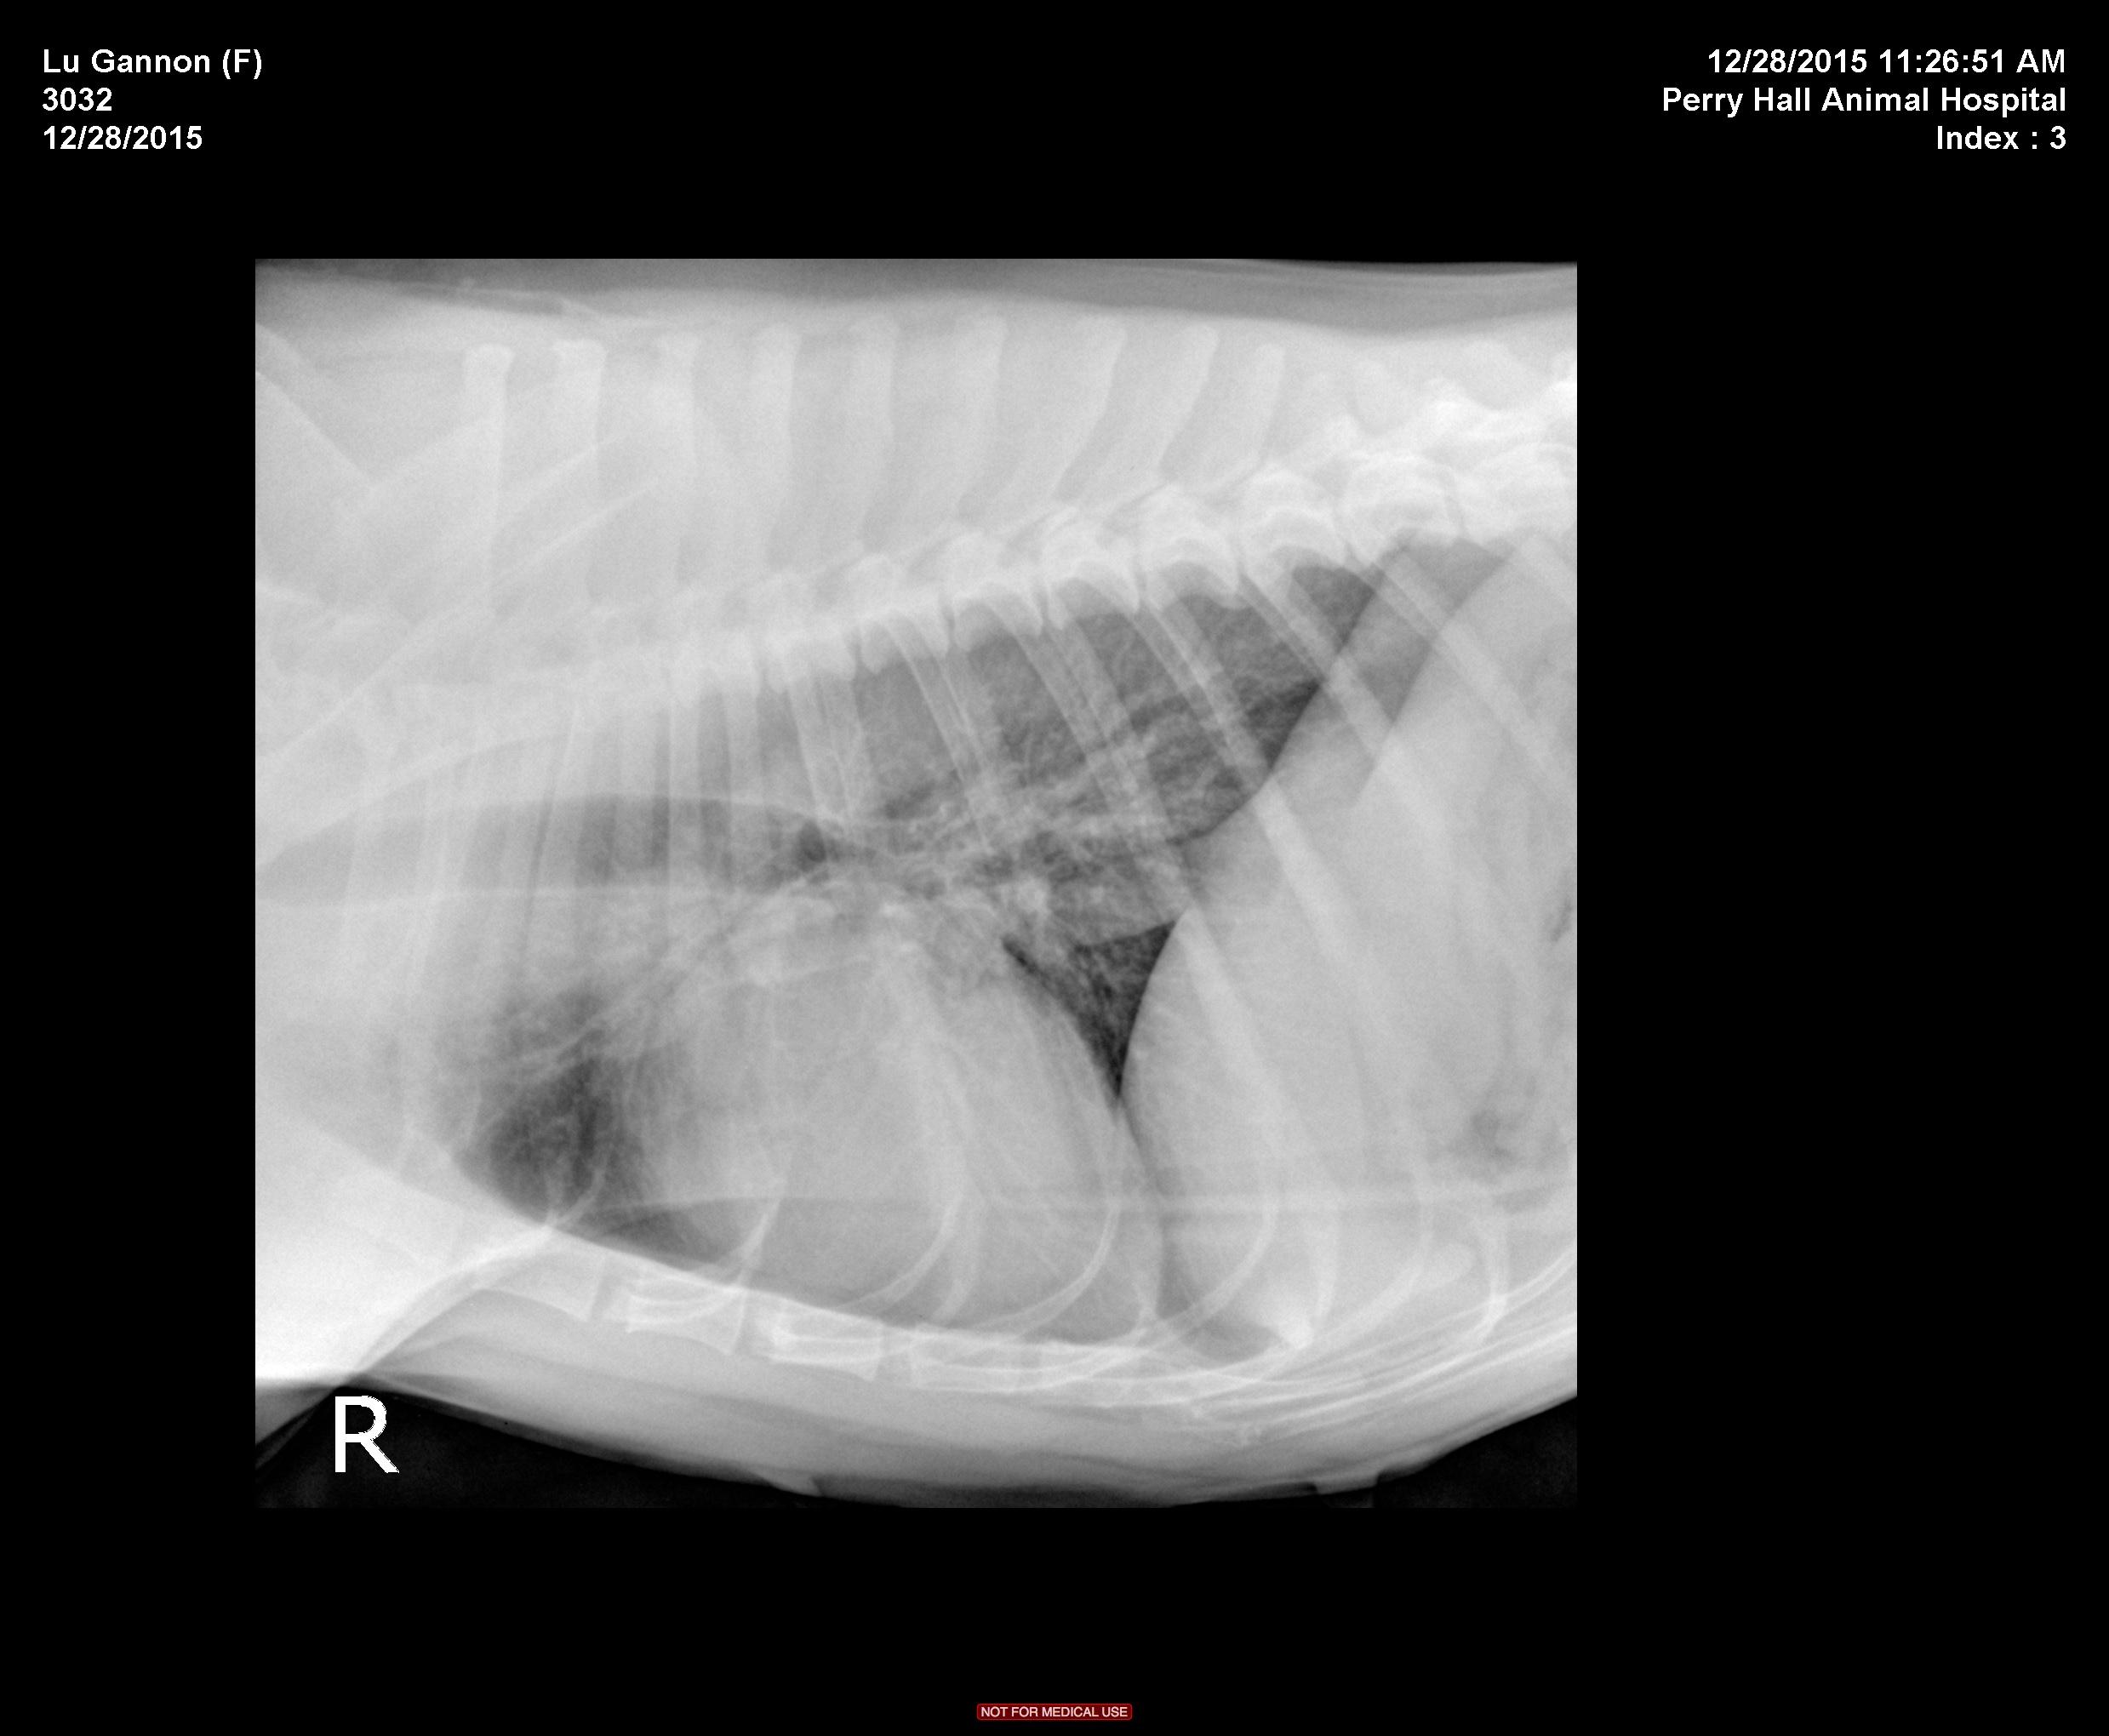

The patient is a 9 year old FS Pitbull with a 3 day history of lethargy and decreased appetite. Has not eaten in 24 hours, decreased water intake. Seems almost ataxic or weak to the owner at home, overall very depressed. Hx of allergies that are controlled.

Physical Exam: Depressed, Temp 101.9. MM pink/slightly tacky. cardiac wnl, lungs wnl on auscultation. BCS 5/9. No abdominal discomfort on palpation. Walking normally x 4 in room but is much less energetic than usual.